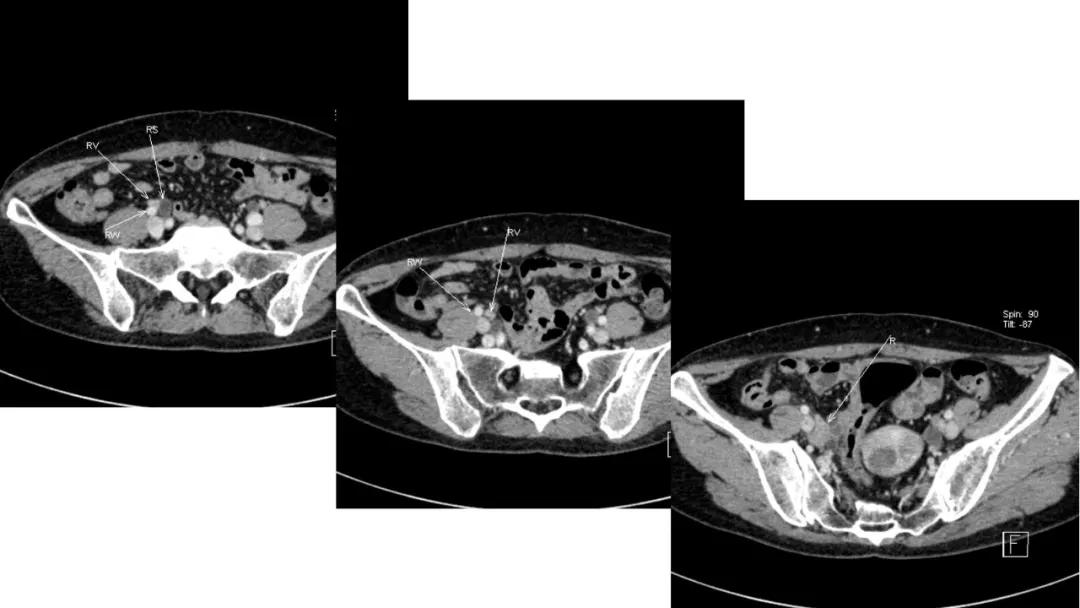

病例10

女,39 岁,体检发现盆腔肿块1月余

CA125:51U/ml

病理:左侧卵巢卵泡膜-纤维瘤